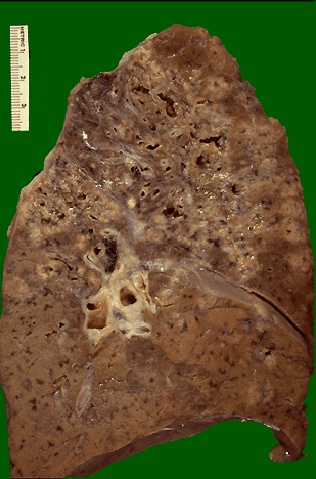

When there is extensive caseation and the granulomas involve a larger bronchus, it is possible for much of the soft, necrotic center to drain out and leave behind a cavity. Cavitation is typical for large granulomas with tuberculosis. Cavitation is more common in the upper lobes.